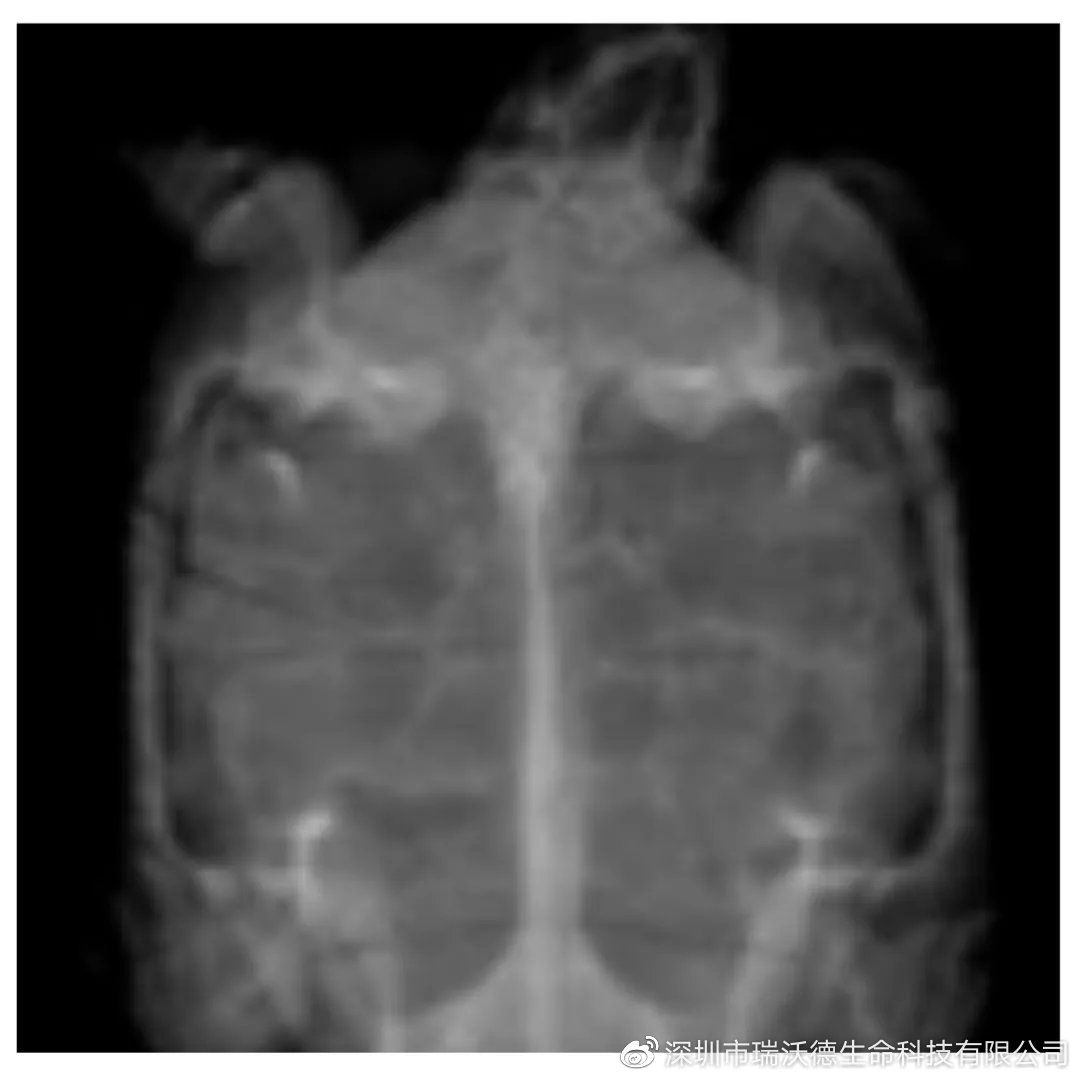

2.3 影像学检查:

对背腹位,右侧位,头尾位进行X光拍摄,在临床体检可见的龟甲断裂处,X光片中亦可见龟甲裂开的痕迹。未见明显其他异常。